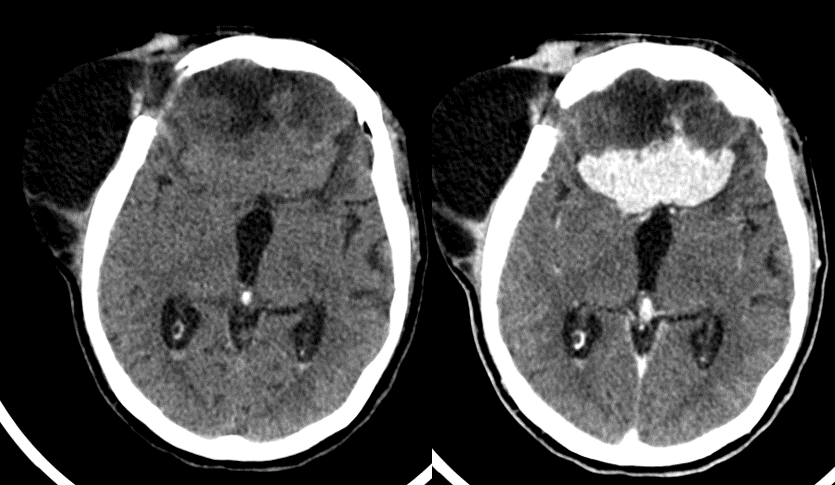

Figura 2.  En la angiografía cerebral se observa la vascularización de la masa desde arterias oftálmicas, cerebrales anteriores, maxilares y meníngeas.